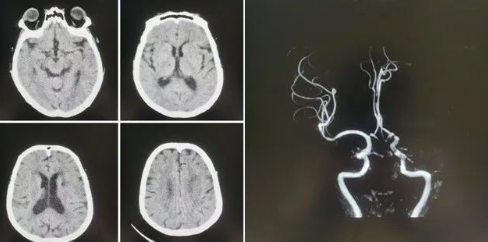

品質國文丨國文醫(yī)院神經介入科成功實施高難度機械取栓術

近日,國文醫(yī)院神經介入科團隊成功實施了一例高難度的腦血栓機械取栓術,為一名急性腦梗死患者打通了“生命通道”。這一手術的成功,不僅標志著國文醫(yī)院在急性缺血性腦卒中救治領域的技術水平邁上了新臺階,也為區(qū)域卒中中心建設增添了新的里程碑。 閱讀量:1397